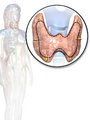

Congenital disorders

Tracheal diverticulum as seen on axial CT imaging

Tracheal agenesis[20] is a rare birth defect in which the trachea fails to develop. The defect is usually fatal though sometimes surgical intervention has been successful.